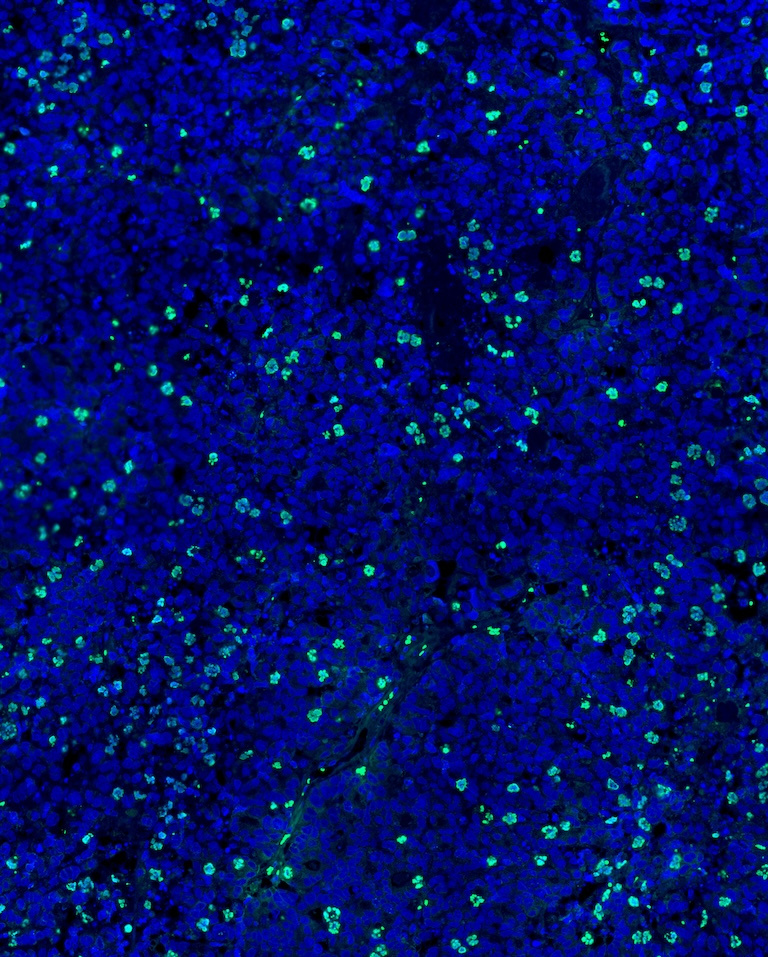

Our work aims to identify optimal combinations of drugs for the treatment of cancer including a combination of a prostate cancer drug called abiraterone and a drug called onvansertib. To better understand how this combination of drugs kills cancer cells, human prostate cancer tumors were grown in mice, treated with these drugs and then examined under a microscope.

The concept of targeting cell division in tumors is controversial given differential rates of growth between human tumors and cells grown in a dish, however, this image demonstrates that this mechanism of cancer cell killing is achievable in human tumors.